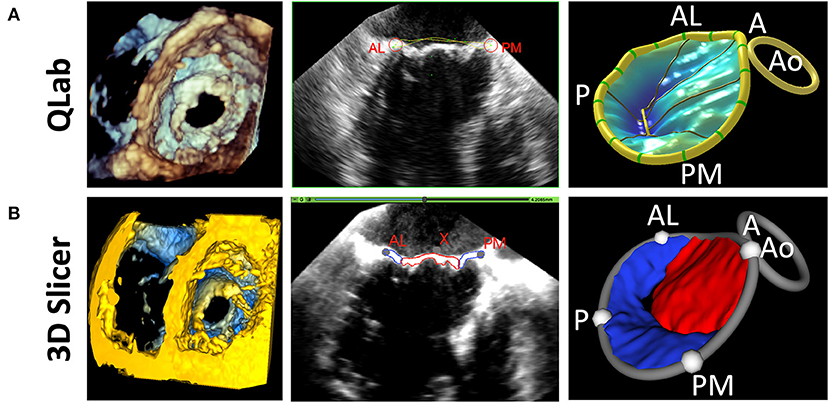

The new Valve Quantification module within SlicerHeart allows semi-automatic quantification of important annular and leaflet metrics (Figures 4, 5 and Supplementary Video 4). A preliminary version of this workflow has been used to generate mitral annular quantification for assessment of suitability for transcatheter mitral valve as we have recently described (23). Custom adaptations of this workflow have been applied to investigations of the tricuspid annulus in hypoplastic left heart syndrome and of the annulus of the native, unrepaired valve in complete atrioventricular canal (26, 49).

Figure 5. Comparison of 3D Slicer vs. QLab Mitral Valve Quantification (MVN). (Left) volume rendering of a mitral valve viewed from the left ventricle in Qlab (A) and 3D Slicer (B); 2D Transesophageal view of the mitral valve highlighting the AL and PM points in Qlab (A) and 3D Slicer (B); 3D Model generated in Qlab (A) and 3D Slicer (B). Qlab, Philips Medical, Andover, MA.